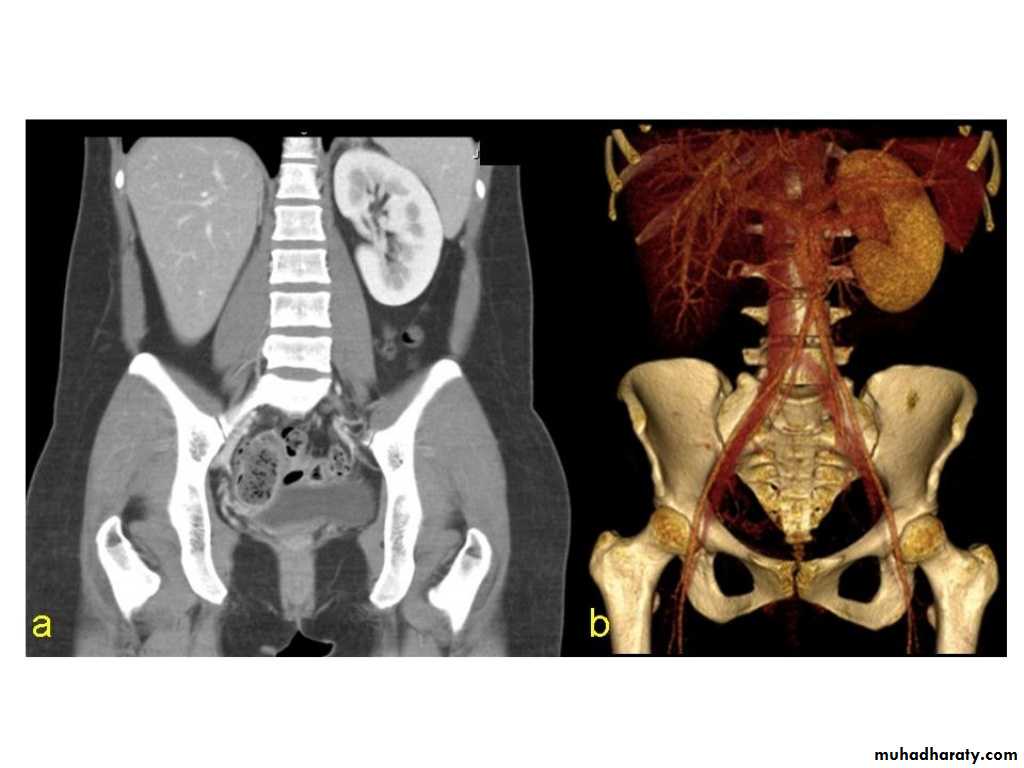

IVU shows

1. The kidneys at low position .2.Close to the spine with long axis parallel to the spine

3. Malrotation manifested by medially directed calyces.

4- The renal pelvis and ureters are anterior and lateral in position.

5- Hydronephrosis and calculi highly associated.